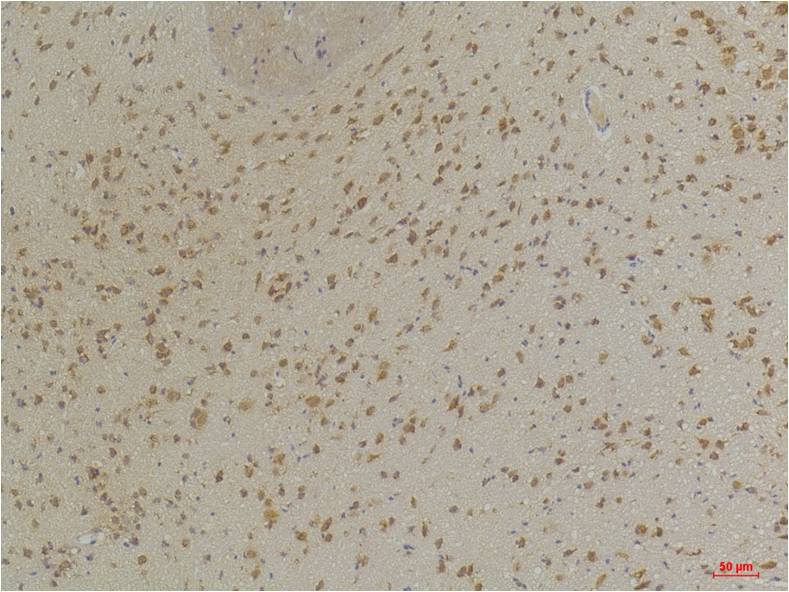

Immunohistochemical analysis of paraffin-embedded Rat BrainTissue using GABA A Receptor α3 (EA286)Rabbit pAb diluted at 1:200.

Immunohistochemical analysis of paraffin-embedded Mouse BrainTissue using GABA A Receptor α3 (EA286)Rabbit pAb diluted at 1:200.